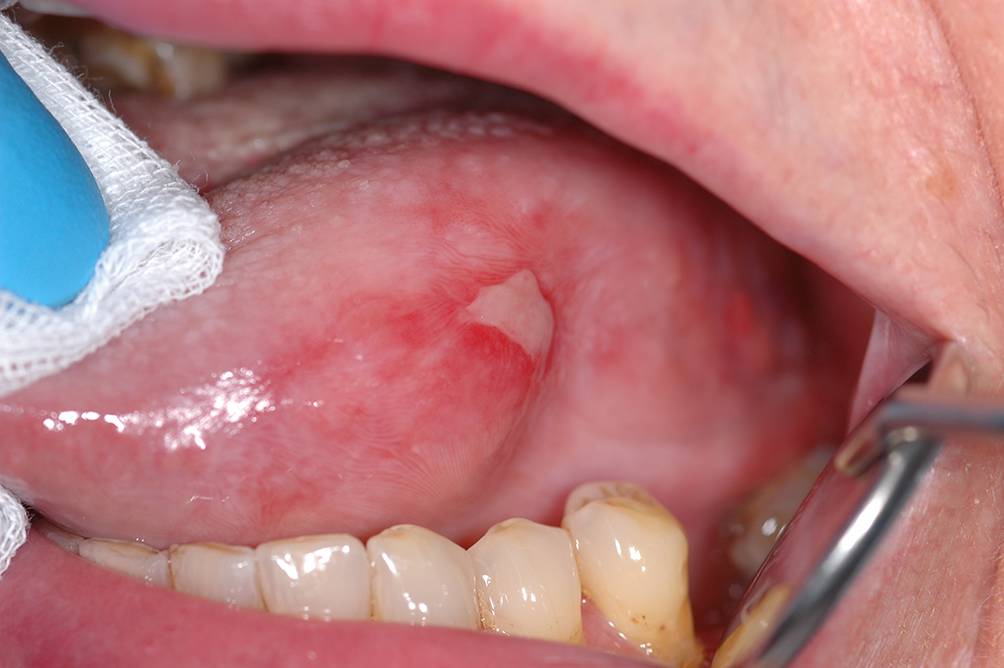

Abb. 8

Ulzerativer Typ eines oralen Lichen planus (OLP) mit großflächiger, fibrinbelegter Ulzeration am linken Zungenrand bei einer 82-jährigen Patientin mit bekanntem OLP. Am linken Zungenrand zeigen sich auch weißliche flächige und weißliche retikuläre Zeichnungen der Mukosa. Diese OLP-Form ist auch differenzialdiagnostisch relevant (Ausschluss von Dysplasien bzw. eines schon etablierten Plattenepithelkarzinoms)

Bild vergrößern